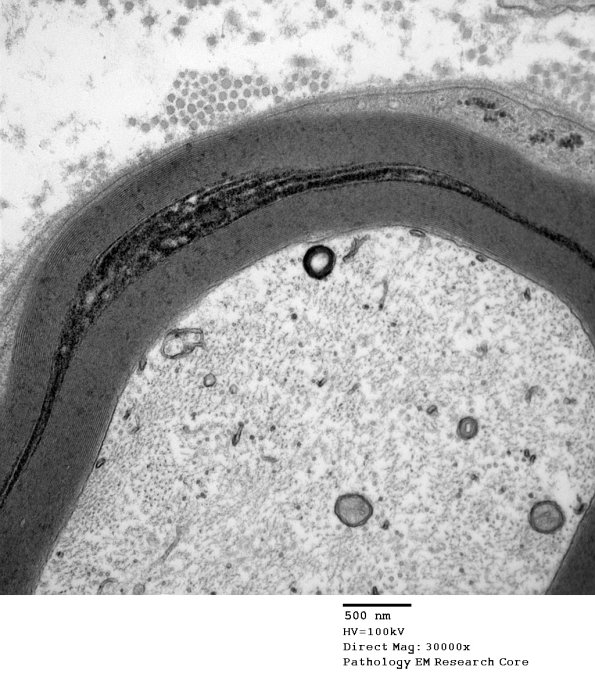

Higher magnification of image #10B1. (electron micrograph)